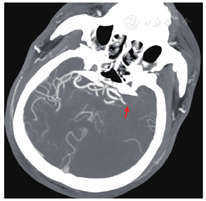

患者男性,57岁,因"胸闷、气短5年,再发加重一周"于2019年4月29日入院。患者5年前(2014年)开始出现胸闷、气短不适,体力活动较前稍有下降,当地医院诊断为"扩张型心肌病",给予对症处理后症状好转,长期口服培哚普利、螺内酯、琥珀酸美托洛尔缓释片。2016年症状再发,当地医院行超声心动图检查:左心室舒张末期内径(left ventricular end-diastolic diameter, LVEDD)63 mm,左心室射血分数(left ventricular ejection fraction, LVEF)44%。冠状动脉造影示:冠状动脉硬化,继续药物治疗,未规律复查。一周前患者感冒后咳嗽、咳痰,胸闷、气短逐渐加重,稍重体力活动即感胸闷,夜间可平卧入睡,偶有阵发性呼吸困难,双下肢无水肿,为进一步诊治就诊我院门诊,门诊以"扩张型心肌病"收治入院。既往发现血压高10年,最高150/120 mmHg(1 mmHg = 0.133 kPa),目前口服培哚普利,血压控制不详。入院体格检查:体温36.5 ℃,脉搏106次/min,呼吸频率21次/min,血压145/97 mmHg。神志清楚,颈软,颈静脉无怒张;双肺呼吸音清,双肺未闻及干湿性啰音;心界不大,心率106次/min,律不齐,可闻及早搏,约15次/min,各瓣膜听诊区未闻及杂音;腹平软,无压痛及反跳痛,肝脾肋下未及;双下肢无水肿,双侧足背动脉搏动对称、良好。辅助检查:血常规:中性粒细胞百分率52.90 %,白细胞计数、红细胞计数、血红蛋白水平、血小板计数均正常;凝血功能:凝血酶原时间17.4 s,活化部分凝血活酶时间(activated partial prothrombin time, APTT)25.9 s,凝血酶原时间国际标准化比值(international normalized ratio, INR)1.15;血生化:血钾4.42 mmol/L,血清肌酐99 μmol/L,肾小球滤过率73 mL/min,血清尿酸631 μmol/L;N末端B型利钠肽前体(N terminal pro-B type natriuretic peptide, NT-pro BNP)2430.00 pg/mL;心肌酶谱:心肌肌钙蛋白T 18 ng/L(参考范围0~14 ng/L);血浆D-二聚体0.34 mg/L。心电图:窦性心动过速,心率103次/min,QRS 142 ms,室内传导延迟,室性期前收缩(室早)。超声心动图:左心房前后径55 mm,右心房前后径52 mm,LVEDD 68 mm,LVEF 36%,左心扩大,右房扩大,室间隔、左室壁运动幅度普遍减低,二、三尖瓣轻-中度返流,肺动脉高压(轻度),左心收缩功能减低,心包少量积液。胸片:肺淤血,肺无实变,右膈光整,左侧胸腔少量积液。主动脉结宽,肺动脉段平,左心房、室增大。心胸比率:0.56。综上诊断:1.扩张型心肌病,心功能Ⅲ级(NYHA心功能分级);2.心律失常,室性期前收缩;3.高血压病3级(极高危)。患者入院后给予沙库巴曲缬沙坦、美托洛尔、呋塞米及螺内酯口服。患者入院后频繁发作室性期前收缩(室早),并发作室性心动过速(室速),给予静脉泵入尼非卡兰可转复为窦性心律,同时加用口服胺碘酮治疗室性心律失常,静脉24 h持续泵入左西孟旦改善心功能。入院第9天(2019年5月8日)行心脏磁共振成像检查(图1)示:LVEDD 71 mm,左心室收缩末期内径(left ventricular end-systolic diameter, LVESD)66 mm,LVEF 15%,右心室射血分数(right ventricular ejection fraction, RVEF)27%,左心室扩大,左心室收缩功能明显减低,右心室收缩功能减低,左心室血栓形成,大小分别为2.2 cm×1.2 cm及2.2 cm×0.7 cm,心肌灌注显像显示心肌未见明显缺血,心肌延迟显像显示室间隔及左室下壁基底段至中间段心肌中层纤维化形成。当日复查超声心动图示:LVEDD 71 mm,LVEF 28%,1、左心扩大,右心房扩大;2、左心室血栓形成(室间隔处可见稍高回声团附着,范围约5.3 cm×1.2 cm);3、室间隔、左室壁运动幅度普遍明显减低;4、二、三尖瓣轻度反流;5、肺动脉高压(轻度);6、左心收缩功能减低;7、心包少量积液。立即给予肝素抗凝治疗,APTT维持40~60s。患者入院后经规范药物治疗,心功能仍为Ⅲ~Ⅳ级,且存在频发室早,短阵室速,抗心律失常药物治疗效果不佳,猝死风险高,遂于入院后第10天(2019年5月9日)行心脏再同步治疗-除颤起搏器(cardiac resynchronization therapy-defibrillator, CRT-D)植入术,术后继续肝素抗凝治疗,术后第3天(2019年5月11日)患者突发失语,右侧肢体偏瘫,肌力0级,考虑急性脑血管意外,急诊行头颈部CTA检查(图2)示:左侧大脑中动脉起始部及以远闭塞,左侧大脑前动脉A2段以远闭塞可能。复查超声心动图提示未见心室血栓,考虑心室血栓脱落所致,神经内科急会诊后建议急诊取栓手术,于发病后约2小时行急诊取栓术,术后患者神志清楚、四肢肌力恢复正常,但仍失语。患者脑梗塞急性期,出血风险高,多次复查心脏彩超未见心室血栓,神经内科会诊建议低剂量抗凝预防血栓形成,术后给予利伐沙班片15 mg,1次/d,口服抗凝治疗,行血浆抗Xa活性测定为0.27IU/L,考虑抗凝有效。取栓术后第2天(2019年5月12日)复查头颈部CTA(图3)提示原左侧大脑中动脉起始部及左侧大脑前动脉A2段以远均显影良好,原闭塞已通畅。患者于2019年5月23日康复出院。随访6个月(见表1),患者LVEDD显著缩小,LVEF及NT-pro BNP水平恢复正常,遗留吐词不清。